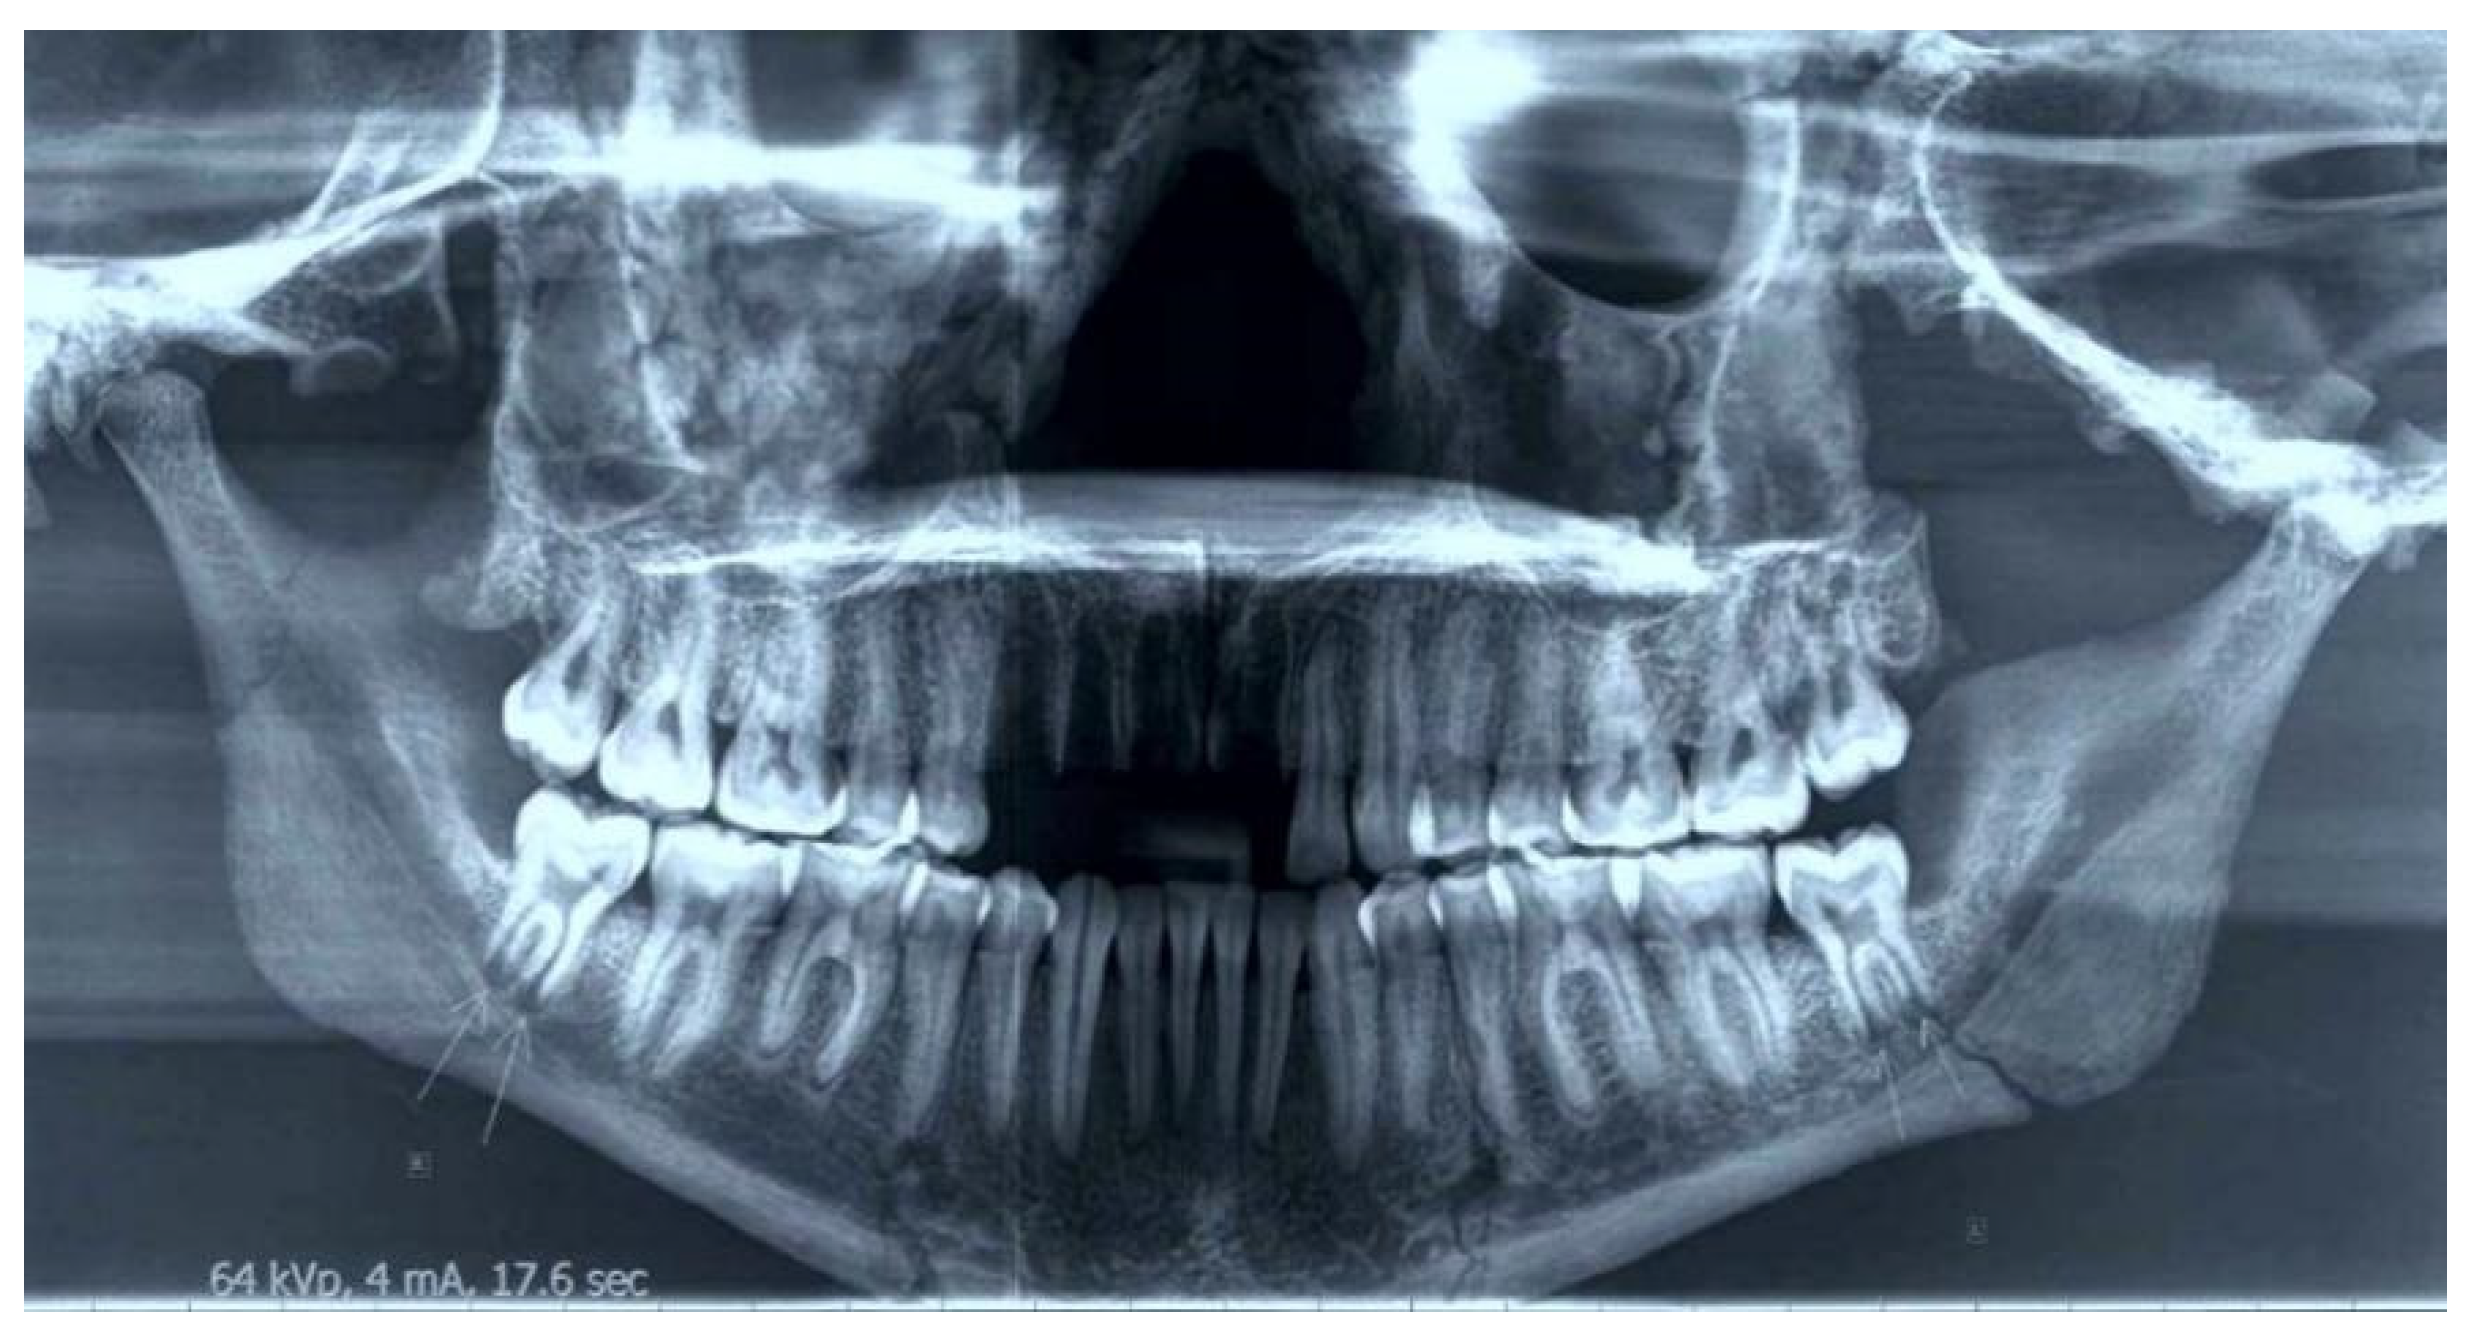

3.4. Dental Pathology

A thorough examination of the dental arches did not evidence signs of major dental pathology (pertaining to caries and periodontal disease, as evidenced by alveolar bone loss), with the exception of a noteworthy abrasion of moderate degree on the lower incisors and first molars (Figure 6). From an orthodontic point of view, class III malocclusion was evidenced by the characteristic Class III molar relationship, anterior crossbite, and relative prognathism of the lower jaw. The macroscopic investigation of the palate identified an island of intra vitam porotic lesions in a mixed pattern of perforations of different size and shape overlapping with areas of diagenetic lesions.

Figure 6. Panoramic radiograph.